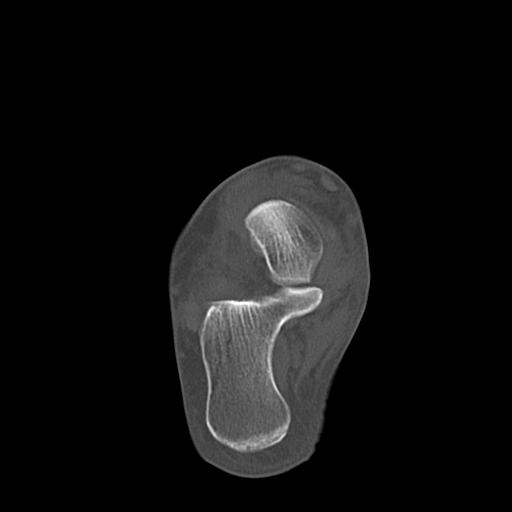

56476 8/28 4R 1/21 2R 左足関節 デジカメ写真 72歳女性 右足関節AS